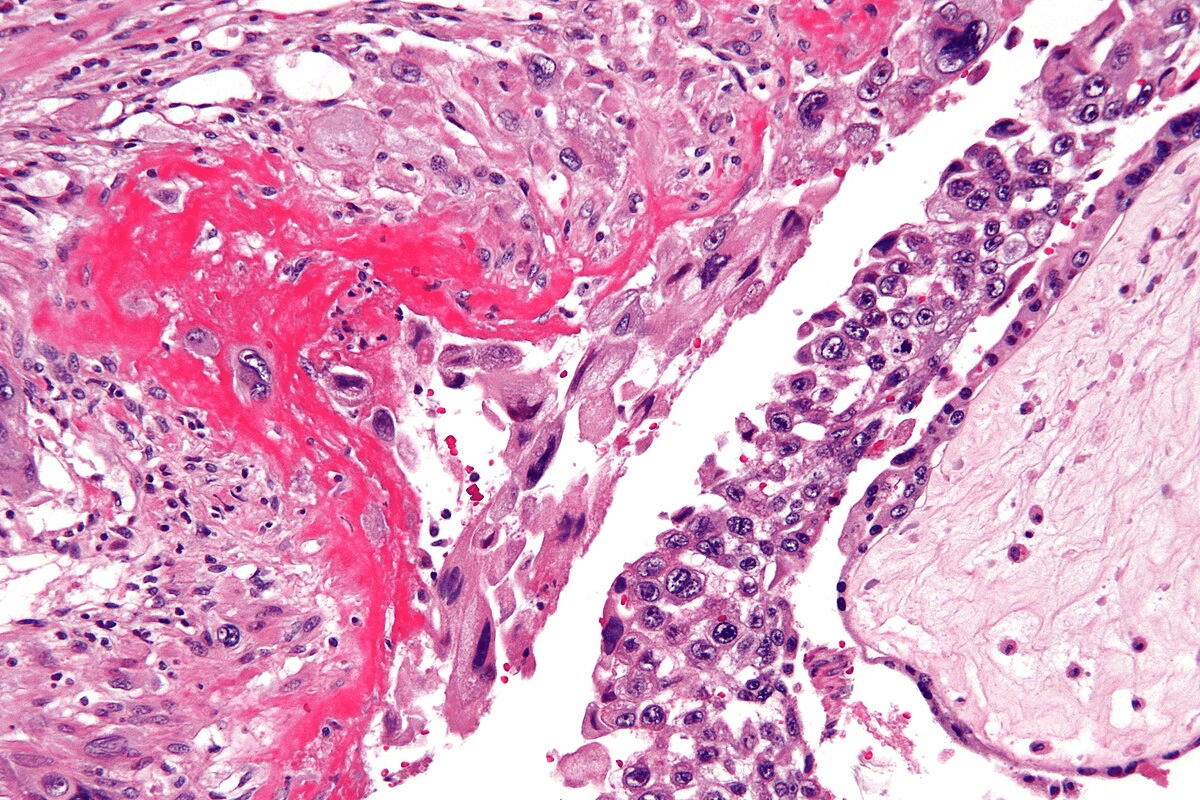

Tissue Biopsy: The Gold Standard

Tissue biopsy is the best way to diagnose ANCA vasculitis. Samples are taken from organs like the kidneys or lungs. Histology shows signs of vasculitis, like inflammation and blood vessel damage.

Biopsy results are very important. They confirm the diagnosis and help decide treatment.